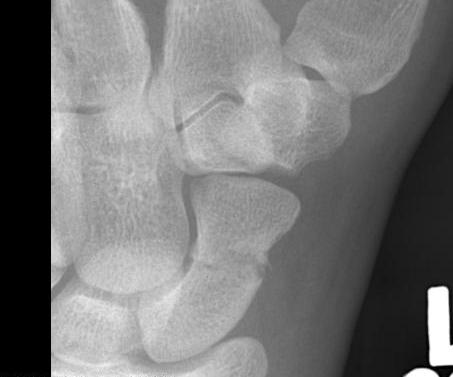

Scaphoid waist fracture 1 mm displaced

Scaphoid fracture with significant displacement

Scaphoid proximal pole fracture